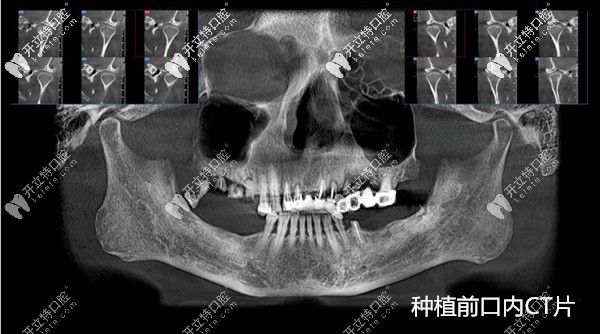

國產(chǎn)百康特種植牙質(zhì)量不輸進口,成功運用在全口即刻種植中

國產(chǎn)百康特種植牙質(zhì)量不輸進口的韓系種植體,適合中國人的牙槽骨、價格還不貴;而且不止是能做傳統(tǒng)的單顆種植牙,還成功的運用在了全口即刻種植、即刻修復(fù)中,有真實案例為證哦!